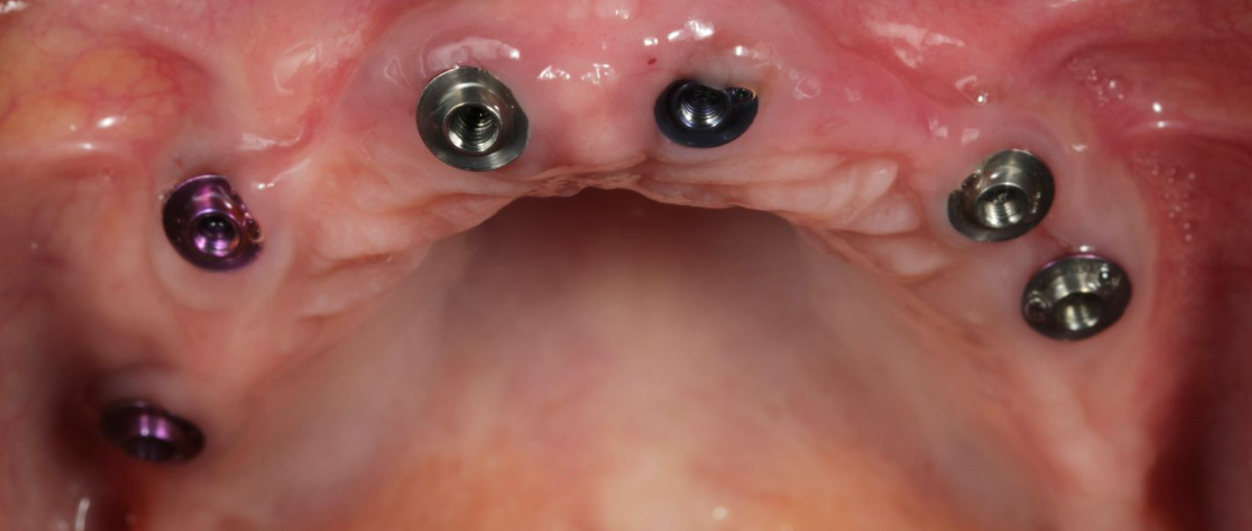

Six standard-diameter Neobiotech dental implants were placed in the maxilla; no narrow-diameter implants were used.

After the completion of the osseointegration period, straight XGATE V-Type multi-units were selected to manufacture the permanent restoration.

Based on the thickness of the soft tissues, the patient received:

- MUA V-type – 1 mm – in positions 21, 24, 26 and 11

- MUA V-type – 3 mm – in positions 13 and 17

At implant sites 16 and 23, an angled screw channel technique using Torx-type screws was employed to optimize the positioning of the screw access hole.